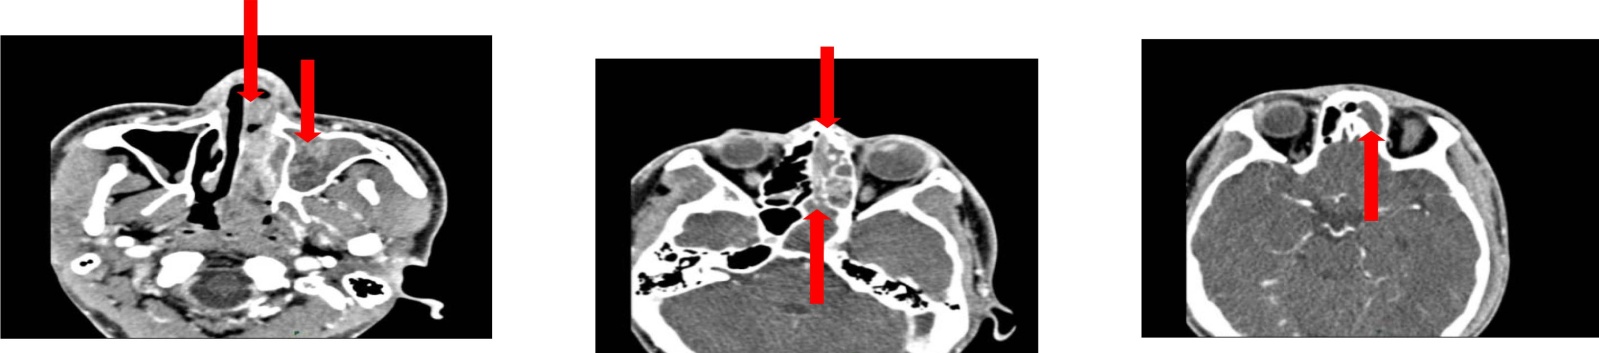

例2:患者男,34岁。因“鼻塞、流涕、头痛3月”2024年6月11日入院,无鼻腔出血或涕中带血,无嗅觉减退,无体重减轻,既往体健。查体:右侧鼻腔见新生物。副鼻窦CT平扫及增强扫描:右侧鼻腔–上颌窦累及眼眶内下部,鼻翼软组织增厚,考虑肿瘤性病变;鼻咽右侧壁稍厚;双侧上颌窦、蝶窦、筛窦及额窦炎(见图3)。余检查结果未见异常。于全麻下行鼻内镜下鼻窦开放术 + 鼻腔鼻窦肿物切除术。术中见右侧鼻腔弥漫性肿物,右侧鼻腔结构不清,向前达鼻前庭,向后至鼻咽部,累及右侧圆枕及咽隐窝,将鼻腔肿物切除后,送术中冰冻病理,提示:间叶源性肿瘤,待石蜡及免疫组化。遂进行多学科讨论,考虑恶性肿瘤可能性大,需待石蜡病理及免疫组化结果,再拟定下一步诊疗方案,术后常规病理示:(右鼻腔)小圆细胞恶性肿瘤,结合免疫组化倾向尤文肉瘤/PNET;免疫组化:CD99(+),F1i-1(+),INSM1(-),Ki-67(+, 60%),Vimentin(+),Myogenin(局灶+),CD3(-),S-100(-),CD20(-),CD79a(-),LCA(-),CK(-),Desmin(-),MyoD1(-),CD34(-),Syn(-),NKX2.2(-)。原位杂交:EBER(-) (见图4),未于我院行放化疗。现术后1年余,电话随访,诉于当地医院规律放化疗,现无复发及转移征象。

Figure 3. Non-contrast and contrast-enhanced paranasal sinus CT scan: The right nasal cavity-maxillary sinus involving the inferomedial orbit with thickened soft tissue of the nasal ala, suggestive of a neoplastic lesion

3. 鼻部CT右侧鼻腔–上颌窦累及眼眶内下部,鼻翼软组织增厚,考虑肿瘤性病变